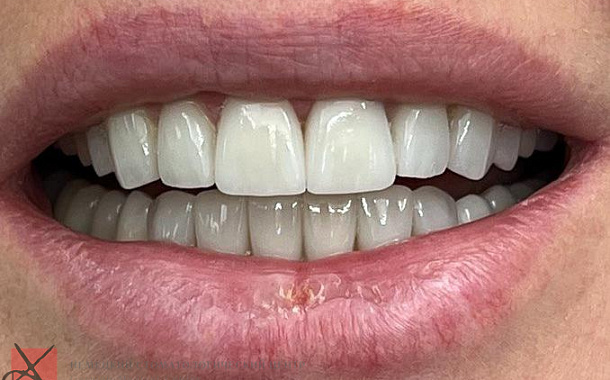

Изготовление винирова

Процесс изготовления керамических виниров состоит из нескольких этапов. Когда определены показания к восстановлению зубов винирами, снимается слепок зубов, отливаются лабораторные челюсти, моделируется макет будущих виниров. Затем с данных восковых реконструкций снимается дублирующий слепок, с помощью которого доктор изготавливает индивидуальный шаблон для препарирования зубов. Это позволяет препарировать зубы намного более щадящим и точным образом. После этого этапа зубной техник получает модель, на которой уже он готовит окончательные виниры. После этого доктору остается лишь зафиксировать готовые реставрации в полости рта пациента.Установка винира на зубы